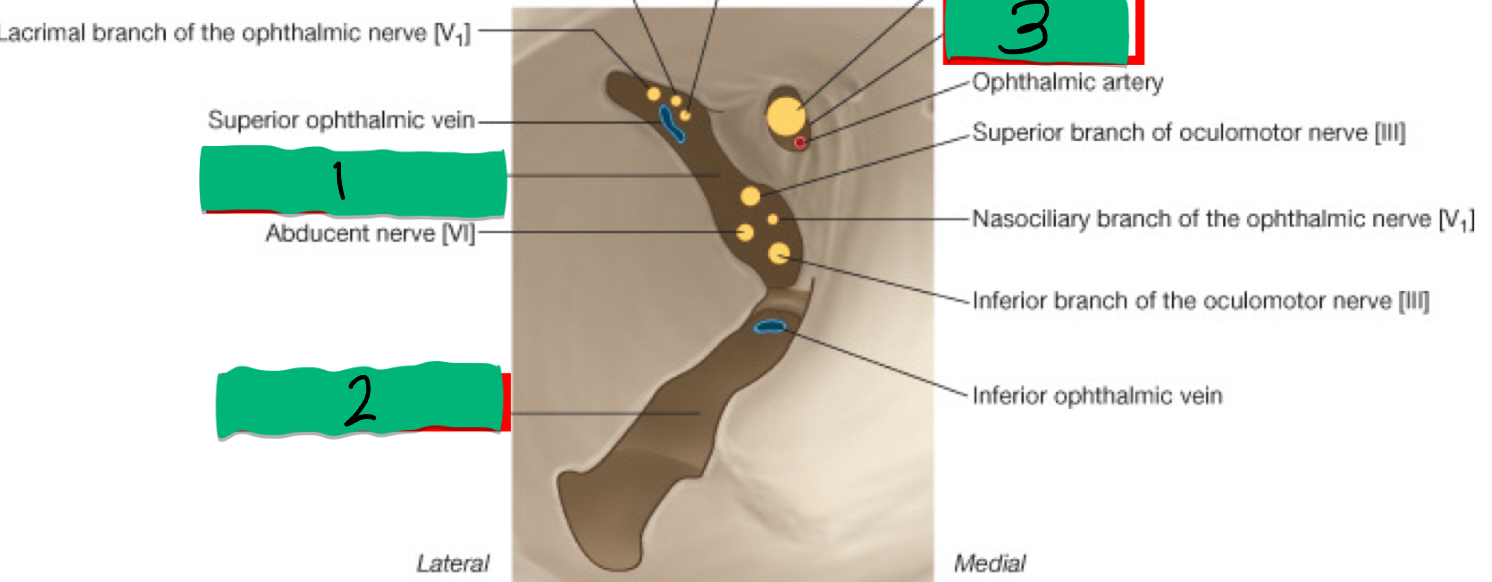

Abducens n. (CN VI) function and exit:

GENERAL MOTOR: Lateral Rectus m.

superior orbital fissure

CN V1 – Ophthalmic Division function and exit:

GENERAL SENSORY: Cornea, conjunctiva, nose, upper eyelid, forehead, anterior scalp

Oculomotor n. (CN III) function and exit:

GENERAL MOTOR: 5 extraocular muscles

VISCERAL MOTOR (Parasympathetic):

Sphincter pupillae and Ciliary muscles